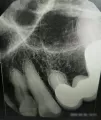

Здравствуйте! При лечении зуба в частной клинике стоматолог увидел на снимке соседний зуб с не до конца пройденными каналами. Кист при этом нет. Сказал, нужно перелечить, но 100% гарантии не дает. Скажите, пожалуйста, насколько рискованно третий раз перелечивать каналы, если зуб не беспокоит? Можно ли потерять при этом зуб?

Добрый день. Перелечивать не опасно, если при этом процедуру проводит грамотный терапевт. В любом случае, зуб необходимо перелечить, так как , на верхушках развивается воспалительный процесс, лечение вам предстоит. Если это будет во время обострения или, того хуже, после образования кисты, то исход процедуры непредсказуемый. Что касается гарантий на перелечивание зуба, доктор прав, он обязан вас предупредить, что во время распломбировки, возможно, всплывут подводные камни в качестве перфорации. Необходимо понять, насколько возможно его распломбировать, так как существуют зубы ранее запломбированные старым неправильным советским методом (резорцин-фармалин), и на такие зубы вообще нет никаких гарантий. Но ваша задача все-таки постараться спасти зуб, то есть перелечить.